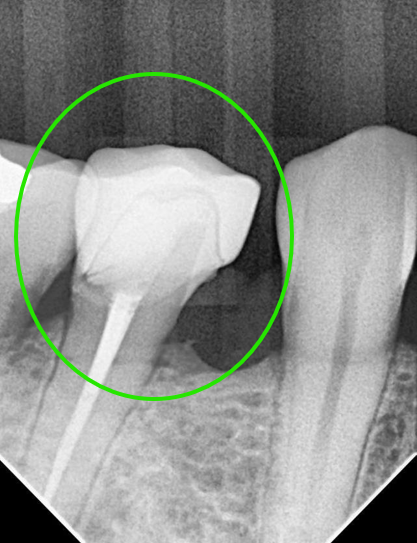

Surgical Microscope (20x Precision)

At Richmond Dental Spa, We see what others miss. Microscopic accuracy ensures a perfect, bacteria-proof seal that prevents future decay.

Dual-Wavelength Laser (Er:YAG + Nd:YAG)2

We use Fotona: Er:YAG to gently reach deep lesions and Nd:YAG to sterilize the area and ensure a perfectly dry field for bonding.